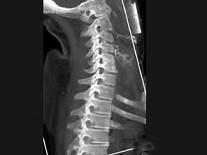

问题 男,35岁,反复颈部不适20余年,结合图像,最可能的诊断是?(?)

选项 A.颈椎椎体融合 B.颈椎结核 C.颈椎退行性变 D.颈椎压缩性骨折 E.颈椎骨转移瘤

答案 A